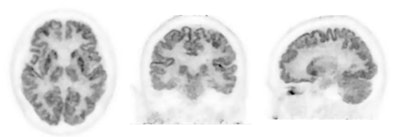

Three FDG-PET scans acquired on PositView SET-5002 showing horizontal, coronal, and sagittal cross-sections.Courtesy of Institute of Advanced Clinical Medicine, Kindai University Hospital; Shimadzu

PositView SET-5002 PET features a PET detector ring with an inner diameter of 28 cm, enabling it to capture images closer to target locations than whole-body PET systems and at an increased resolution of about a factor of two, according to Shimadzu.